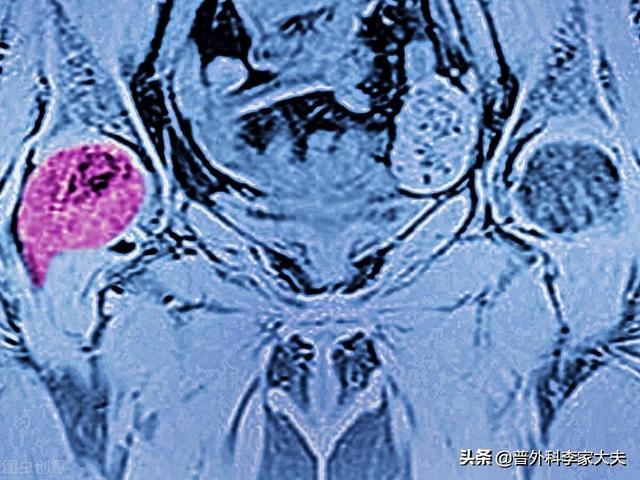

脊椎に発生する骨転移が最も多く(34%)、次いで骨盤(20%)、下肢の長骨(12%)。。

骨転移はどのような痛みに注意すべきですか?骨転移は悪性腫瘍の末期によく見られる症状で、体の他の部位にある原発腫瘍が血液やリンパ液の経路を通って骨に転移し、骨転移を形成することを指します。骨転移は、正常な骨組織が破壊され、腫瘍組織に置き換わっていることを示す。骨転移は病変の特異性により、溶骨型、造骨型、混合型の3つに分類される。骨転移の好発部位は中軸骨(脊椎、骨盤)、肋骨、下部骨幹部で、特に中軸骨が最も多く、これはこの部位の血液供給の特徴と関係しています。下の円のように骨転移が多発し、脊椎の状態が悪い。

骨転移で起こる症状にはどのようなものがありますか?最初の症状は痛みです。骨転移を起こした部位は骨が破壊されるために痛みを感じますが、最初ははっきりした症状がなかったり、断続的な痛みだったりしますが、腫瘍が正常な骨をどんどん破壊して徐々に悪くなっていくため、転移部位の痛みも徐々に悪くなっていきます。臨床的には、体のある部分の骨の痛みで、悪性腫瘍の骨転移という症例に出くわすことがあります。以前、ある症例に出会ったのですが、40歳で、肩が痛く、五十肩かと思い、薬用オイルを数日揉んでも改善が見られず、ますます痛みが強くなったので、病院で検査をしたところ、MRIを撮ったところ、肩甲骨が(腫瘍の)かけらに食べられており、骨転移を考え、胸部CTを撮ったところ、右肺に結節があり、生検をして病理検査をしたところ、肺がんの骨転移でした。その内容は以下の通りである。